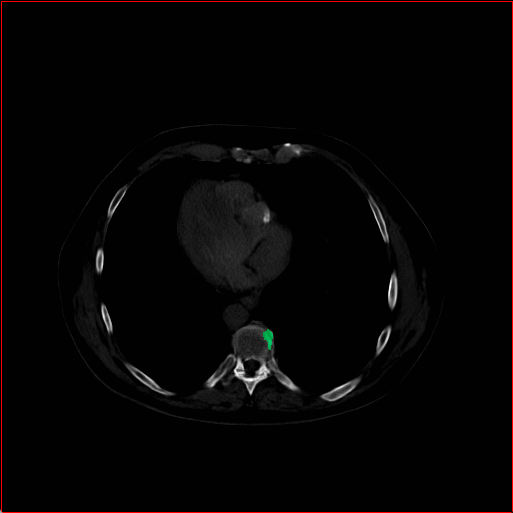

Figure 2: Qualitative comparison across axial (top row), sagittal (middle row), and coronal (bottom row) views. Columns correspond to different methods. MAISI-DDPM and MAISI-v2 in this figure are unconditional synthesis which do not use ControlNet or segmentation maps.

Qualitative Evaluation:

Figure 2 presents representative slices from the axial, sagittal, and coronal planes. GenerateCT (hamamci2024generatect) is a 2D model, so it lacks inter-slice consistency, leading to poor image quality in the sagittal and coronal views. MedSyn (xu2024medsyn) produces noticeably blurry results with mosaic-like artifacts, such as region inside the red box. HA-GAN (sun2022hierarchical) generates visually sharp images but with mosaic-like artifacts, such as region inside the red box. Also, its voxel spacing is not available, which limits its applicability in real-world medical imaging tasks. Moreover, all three methods are restricted to synthesizing small anatomical regions. In contrast, both MAISI and MAISI-v2 are capable of generating high-quality 3D volumes that span larger body regions while preserving fine anatomical details and realistic structure.